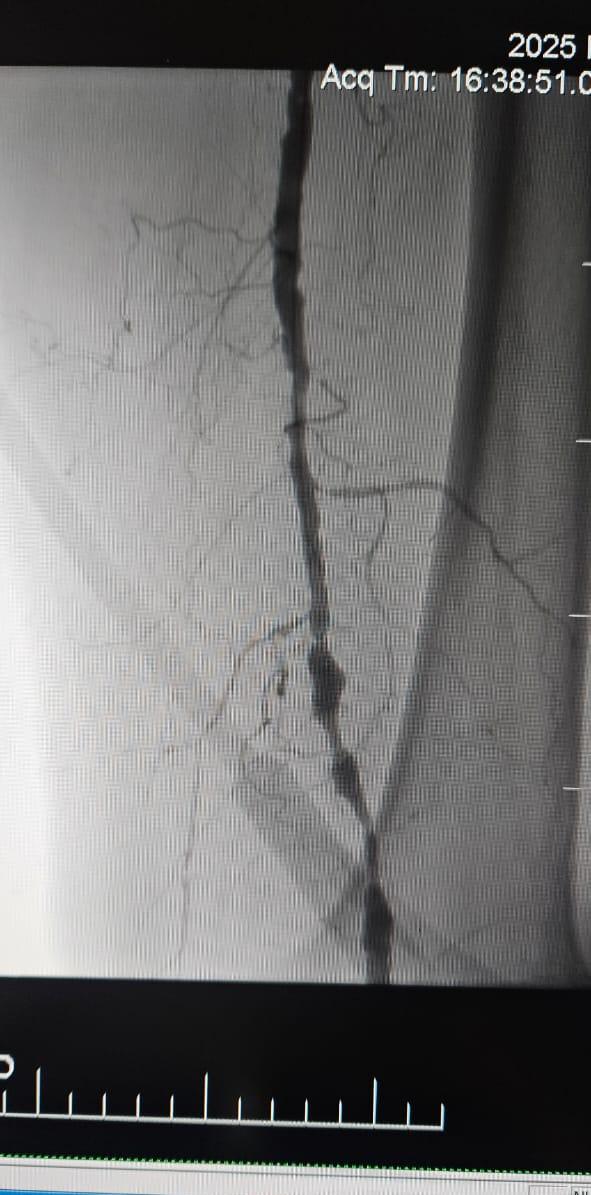

Мы рады поделиться успешным случаем из больницы в Батуми, Грузия, где 78-летняя пациентка с критической ишемией конечностей (CLI), вызванной хронической полной окклюзией артерии нижней конечности, показала значительное клиническое улучшение после лечения с помощью периферийной системы расширенного баллона ThorCrack IVL.

Этот случай подчеркивает клиническую ценность внутрисосудистой литотрипсии (IVL) в лечении сложных случаев CLI с хронической окклюзией длинного сегмента-особенно у пациентов с тяжелой кальцификацией, где традиционные баллоны или устройства для атерэктомии могут иметь ограниченную эффективность.